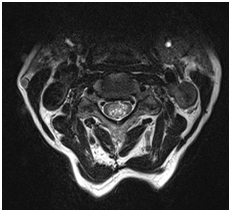

Ependimoma a gerincvelő. MR minta degeneratív változások a nyaki gerinc, a C5-C6 lemez extrudálás, C6-C7, C7-Th1.

T2VI T1 (kontraszt)

A szklerózis multiplex. Foci demielinálódás a gerincvelőben.

T1VI T2VI T1 (kontraszt)

gerinc kavernoma

Epidurális vérömleny a nyaki gerinc

Rheumatoid arthritis atlanto-axiális közös.

Mr képet spondylosis, extrudált lemez C3-C4, C4-C5, C5-C6, C6-C7.

Syringomyelic ciszta gerincvelő

Veleszületett rendellenességek: hipoplázia szervek C5, C6, C7 csigolyák; részleges konkrestsentsiya (fúziós) tel C5-C7 csigolyák.